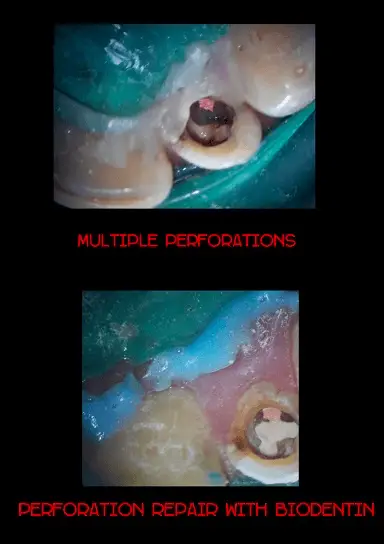

Perforation Repair Under Dental Operating Microscope

Patient presented with slight numbness and pain on chewing in the lower premolar region due to which he had difficulty in eating food. Radiographic examination revealed attempted root canal treatment. When operated under Dental Operating Microscope multiple perforations were seen. The perforations were sealed with BIODENTIN and the root canal treatment was completed successfully. The patient went back home with proper functioning teeth.